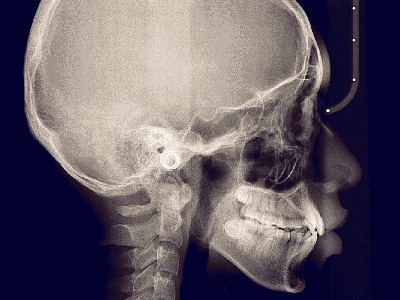

We practice the ALARA principle; (As low as Reasonably Achievable) all scans are restricted to the “Field of View” of your dentist’s prescription. It is taken using (1) pulsed x-ray exposure protocols, (2) real-time-automatic exposure control of the x-ray dose based on the patient’s actual bone density & (3) high resolution digital x-ray image sensors. These factors lead to a significant reduction in x-ray exposure equivalent to only 10% of the x-ray dose of a medical CT-Scan.

The aforementioned technology is inherent in the “myRay X9 CBCT Scan” that we use. myRay X9 is an Italian-made Oral Maxillofacial CT-Scan, certified compliant by European, Japan, USA and other international authorities in radiation safety.